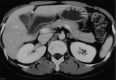

Figure 2

Abdominal CT. (A) Demonstrated diffuse hepatosplenomegaly. (B) Demonstrated left paraaortic lymphadenopathy (arrow).